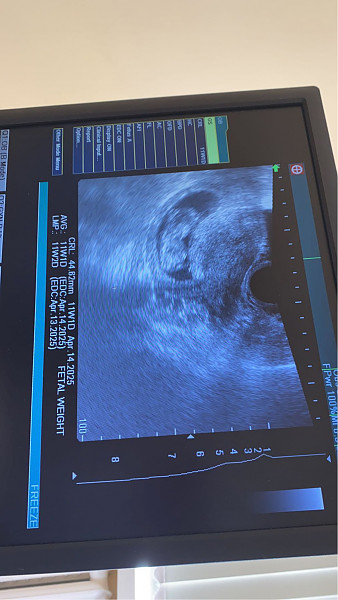

- Nėštumas